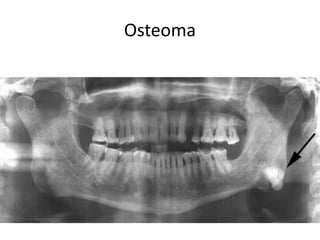

Osteoma

• ♂ >♀, 40 y & above

• Asymptomatic until interferes with function

• Overlying mucosa is normal and freely mobile.

• Mand. > Max. & Paranasal sinuses

frontoethmoidal

• Well-defined, RO (Compact),

Internal RL core (Cancellous)

A panoramic radiograph shows an osteoma

in the right mandibular angle region